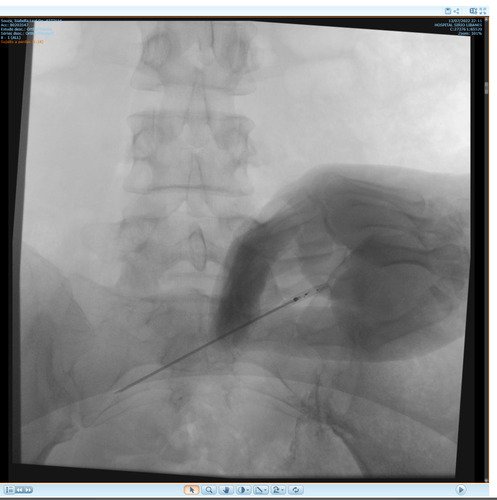

Não sei por onde começar porque e uma história longa e vou tentar resumir, fiquei meses tentando descobrir que eu tinha fibromialgia, porém eu não tenho só isso, tive edemas na coluna, problemas na lombar, e até derrame pleural eu tive, eu pago aluguel que e 1300 mais o condominio que e 450, fora que eu me planejei e não tenho familia pra apoiar entre outras coisas, quando me mudei e planejei pra poder ter o proprio ape eu não sabia que do nada iria ficar doente, em março de 2023 eu pego as chaves mas até la ta dificil, fiz emprestimo e várias outras coisas porque só a medicação de durogesic que eu uso e restiva um a caixa e 650 e o outro 300, podem pesquisar, após um procedimento na lombar cirurgico pra tentar aliviar a dor descobri uma necrose asseptica na cabeça dos dois femur, com risco de ter que colocar uma protese, até pouco tempo estava de muleta, só podia ficar sentada, e mesmo a dor e muito forte, eu ainda não sei a tal outra doença que eu tenho, já aconteceu de eu entrar na emergência e ficar na UTI, tive mais de 10 internações no hospital e não e mentira, minha maior luta e conseguir tratar essa necrose, poder voltar a praticar esportes, sei que tem gente que precisa muito mais mas eu cheguei no meu limite e to até com um aluguel atrasado, todas as coisas que eu estiver pagando eu vou colocar nota fiscal porque eu não to aqui pra fazer ninguém de trouxa, vou colocar exame, fotos de internação entre outras coisas que posso, porque tem algumas que não posso devido porque não quero imagem negativa para local de trabalho (e aonde eu trabalho eles estão me ajudando e muito), e de acordo de como for funcionando a vakinha eu vou vendo se aumento, eu só queria me livrar dessas contas sufocantes primeiro, e agora os médicos estão lutando pra descobrir a outra doença que tenho além dessa da necrose que ta me deixando muito mal e que a fibromialgia atrapalha a descobrir, sei que e chato porque já pedi ajuda 2 vezes, mas conversei com amigos e infelizmente eu não tenho outra opção a não ser pedir ajuda, vou colocar exame de tudo etc, o valor até de emprestimos que estou devendo e tudo mais, e podem me perguntar qualquer coisa que eu respondo e claro, vou postar nota fiscal pra provar que to pagando o que to mostrando, eu to no meu limite, e não e fácil, eu ficava 3 dias seguidos sem conseguir dormir e os médicos não conseguiam descobrir e ainda sigo firme no tratamento porque vou encontrar uma resposta e não posso desistir do tratamento, eu poderia fazer um textao aqui mas com poucas palavras já consigo ser direta, obrigada a quem ajuda e continua me apoiando desde o começo e pra quem não gosta e não acredita e só não ajudar, ninguém vai ficar inventando internações etc pra ficar ai pedindo dinheiro de graça pra ostentar, não gosta só não infernizar, só cada um sabe o sofrimento que ta passando na própria pele e a sua luta diária, agradeço se puder ajudar, aceito tudo que seja positivo e desejo o dobro de bom pra cada um.